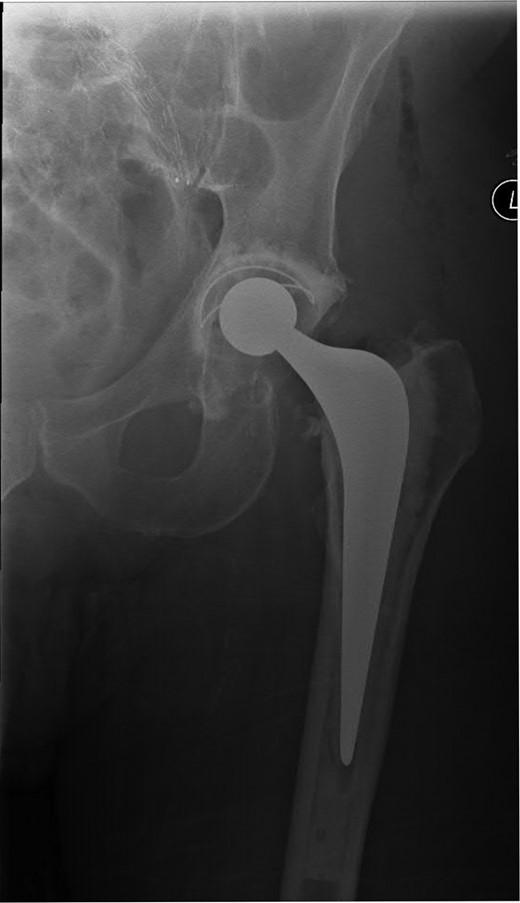

A 74-year-old male was admitted with an intracapsular fractured left neck of femur (Fig. 1). According to the NICE guidelines, he received a cemented THR (Fig. 2) via the posterior approach in the lateral decubitus position. Five weeks prior, he had an EVAR for a leaking AAA. Due to a calcified, narrow right common iliac artery (CIA), the EVAR consisted of a left aortouniiliac endograft with coil embolization of the right CIA and a femoro-femoral crossover graft (Figs 3 and 4).

AP radiograph of the lumbar spine demonstrating the aortouniiliac EVAR with coil embolization of the right CIA.

Lateral radiograph of the lumbar spine demonstrating the aortouniiliac EVAR with coil embolization of the right CIA.